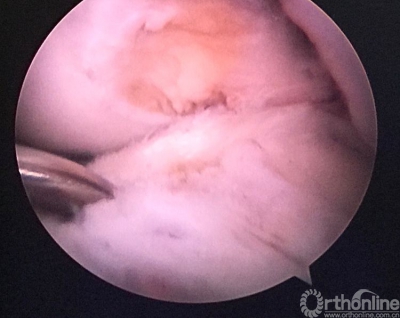

重建后关节镜检查见ACL的走向及张力等均好。

关节镜从前内入路进入,清晰的见到原胫骨隧道内口与返修后的相距较远。

返修手术后检查患者的膝关节前抽屉试验(-),Lachman(-)。